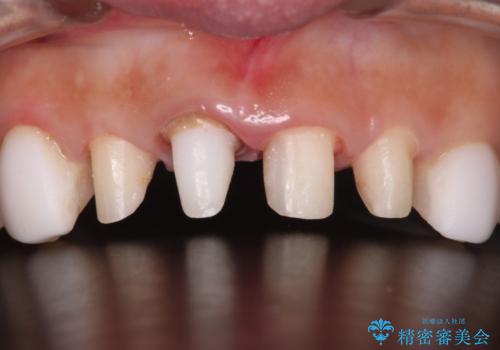

- 他院で治療した前歯の色が気になるということで来院された患者様です。前歯に色の差があり、レントゲンから内部にう蝕も見られたため、審美性に優れ、う蝕になりにくいオールセラミッククラウンで治療いたしました。